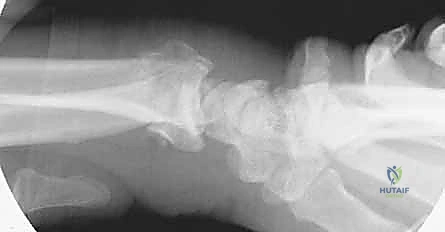

- الأشعة السينية (X-rays): بأوضاع متعددة لتقييم زوايا الكسر ومقدار الانهيار العظمي.

| الصفيحة الجسرية (Bridge Plating) | صفيحة طويلة تمتد من الساعد وتعبر المفصل لتثبت في عظام اليد. | الكسور شديدة التفتت، فقدان العظم، والإصابات المتعددة. | يتطلب جراحة ثانية لإزالة الصفيحة بعد التئام العظم (بعد 3-4 أشهر). |

مبدأ عمل الصفيحة الجسرية (Distraction Ligamentotaxis)

تعتمد هذه التقنية المتقدمة على مبدأ إبقاء المفصل مشدوداً ومثبتاً من الخارج. الصفيحة تعمل كـ "جسر" يعبر فوق منطقة الدمار الشامل في العظم، وترتكز على عظم سليم في الساعد وعظم سليم في اليد. هذا الجسر يمنع العظم المفتت من الانهيار ويسمح للشظايا الصغيرة بالالتئام في مكانها الصحيح بفضل الشد الطبيعي للأربطة المحيطة.

3. إدخال الصفيحة الجسرية (Plate Insertion)

بمهارة فائقة، يتم تمرير الصفيحة المعدنية المصنوعة من التيتانيوم تحت الجلد وفوق الأوتار عبر الشقين، بحيث تعبر مفصل الرسغ بالكامل متجاوزة منطقة الكسر المفتتة دون العبث بها.

يتم تثبيت الصفيحة بقوة باستخدام براغي متطورة (Locking Screws) في عظم الساعد السليم وعظم المشط في اليد. هذه البراغي تلتحم بالصفيحة لتشكل هيكلاً صلباً للغاية لا يتأثر بالحركة.

أثناء العملية، يستخدم الدكتور هطيف جهاز الأشعة المباشر للتأكد من المحاذاة المثالية للعظم واستعادة الطول والزوايا التشريحية الصحيحة للرسغ.